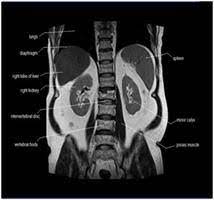

How will you get the test results? The mri of the abdomen will take approximately 60 minutes. What does the procedure involve? In some cases, it may take up to about 2 hours. Abdominal mris are used for a variety of reasons, such as examining:

What do i do after my scan? Newer scanners complete the process in less time. But the magnet is very powerful. In some cases, it may take up to about 2 hours. Do you have to drink anything before a mri scan? Most pelvis mri exams are done in the main hospital, acc or placer clinics. The mri of the abdomen will take approximately 60 minutes. How long to wait after mri? Abdominal mris are used for a variety of reasons, such as examining: How will you get the test results? Please contact the doctor who ordered the test for any test results. What are the risks of an mri of the abdomen? How to prepare for the test: